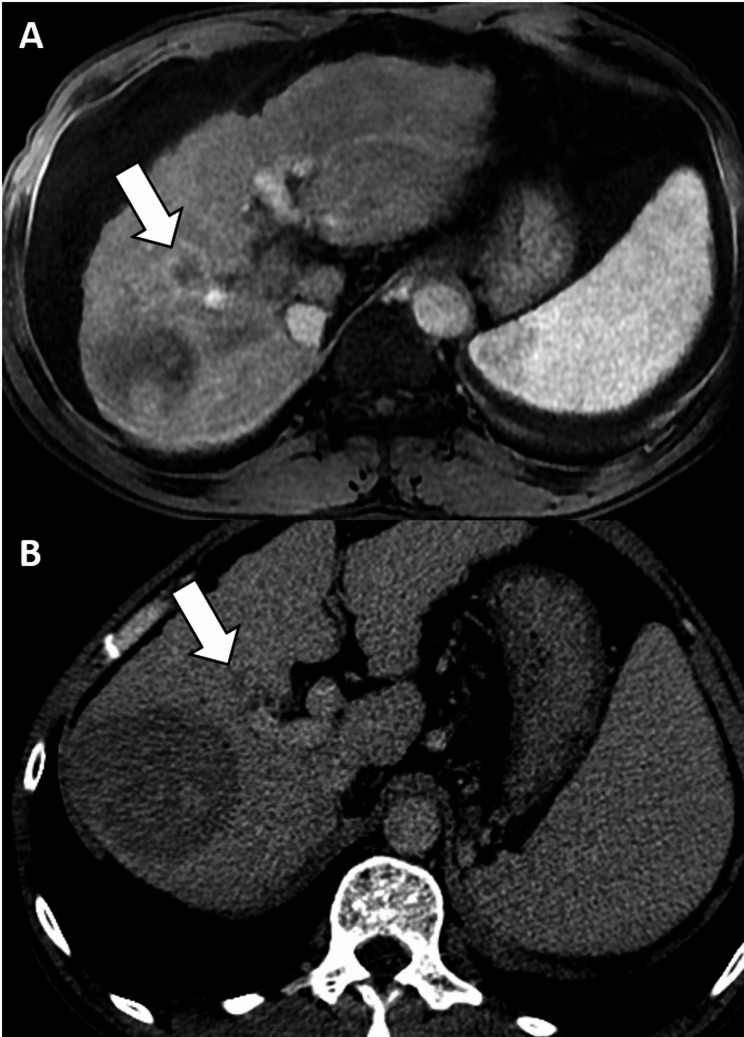

背景:阈值生长(TG)在肝细胞癌(HCC)成像中的应用在主要指南中仍然存在争议。本研究旨在探讨TG在肝成像报告和数据系统(LI-RADS)标准下肝癌诊断中的诊断意义。方法:在这项单中心回顾性研究中,三名放射科医生独立评估了2010年1月至2022年11月期间连续接受肝移植的患者的移植前肝胆剂增强MR图像和先前的CT/MR图像,使用LI-RADS v2018。TG定义为≥50%的尺寸增加≤6个月。肝脏作为参考标准。使用Fisher精确检验比较hcc和非hcc之间的TG频率,并使用Fleiss κ统计评估观察者间的一致性。在考虑TG为主要特征和不考虑TG为主要特征的情况下,评估LI-RADS第5类在HCC诊断中的诊断性能。麦克尼马尔试验用于比较结果。结果:纳入158例患者(平均年龄59.1±7.5岁;130例男性),280例观察(207例hcc, 5例非hcc恶性病变,68例良性病变)。有44例(15.7%)观察到TG。观察者间对TG的一致性为中等(κ = 0.280)。将TG作为主要特征可显著提高LI-RADS第5类诊断HCC的敏感性(33.8% vs. 40.6%)。结论:将TG作为LI-RADS第5类的主要标准可提高肝移植候选人HCC的诊断敏感性,对特异性影响最小。然而,TG显示了一个可变的观察者之间的协议。试验注册:不适用。

Methods: In this single-center retrospective study, three radiologists independently evaluated pre-transplantation hepatobiliary agent-enhanced MR images and prior CT/MR images using LI-RADS v2018 in consecutive patients who underwent liver transplantation between January 2010 and November 2022. TG was defined as a ≥ 50% size increase in ≤ 6 months. Explanted livers served as reference standards. Frequencies of TG between HCCs and non-HCCs were compared using Fisher's exact test, and interobserver agreement was assessed using Fleiss κ statistics. The diagnostic performance of LI-RADS category 5 in the diagnosis of HCC was assessed with and without considering TG as a major feature. McNemar tests were used to compare results.

Results: The cohort included 158 patients (mean age, 59.1 ± 7.5 years; 130 males) with 280 observations (207 HCCs, 5 non-HCC malignancies, and 68 benign lesions). TG was identified in 44 (15.7%) observations. Interobserver agreement on TG was moderate (κ = 0.280). Incorporating TG as a major feature significantly enhanced the sensitivity of LI-RADS category 5 in diagnosing HCC (33.8% vs. 40.6%, p < 0.001) without compromising specificity (100.0% vs. 94.5%, p = 0.125).